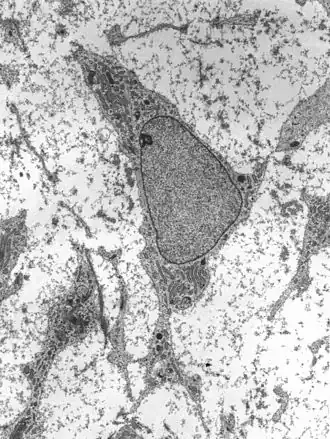

![]() célula madre de adulto. | ||